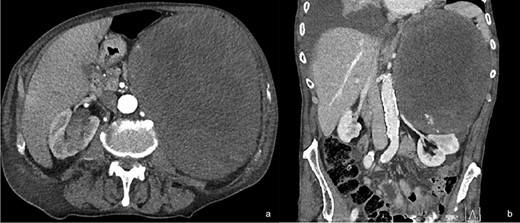

An 83-year-old male patient with no history of hypocoagulative conditions or anticoagulant medications, presented to the hospital after a right thoracic trauma, and was hospitalized for right hemothorax and fracture of the omolateral VII–X ribs. On physical examination, a mass on the left upper abdominal quadrant was incidentally noted. An additional thoracic–abdominal contrast computed tomography (CT) scan documented a left retroperitoneal mass of doubtful renal–adrenal origin, displacing the spleen, the body–tail of the pancreas, the left kidney and the stomach (Fig. 1a and b). No signs of metastatic disease were present.

Contrast CT scan of the abdomen of the patient at his admission in the hospital. Axial view showing a left abdominal mass occupying the left upper abdominal quadrant and displacing down the left kidney (a) and renal artery and vein as shown in the coronal view (b).

The patient reported a previous history of left non-secreting adrenal incidentaloma, diagnosed 10 years before. At the time of diagnosis, the tumor diameter was 2.3 cm, with CT densitometry suggestive for benign adenoma (Fig. 2); the patient had been invited to regular follow-up visits, which he never attended. After 6 years, a new contrast CT demonstrated a growth of the tumor up to 7 cm. The clinical examination had excluded symptoms and signs of adrenal hormonal excess. A new complete evaluation of the endocrine situation was repeated: 1 mg overnight dexamethasone suppression test excluded cortisol excess; pheochromocytoma was excluded by the measurement of urinary fractionated metanephrines; because the patient was hypertensive, aldosterone/renin ratio was performed after 2-month washout from interferent antihypertensive drugs and a primary aldosteronism was excluded; all other laboratory tests were regular. The patient was asymptomatic and decided to discontinue his follow-up, coming back to medical attention the day of the trauma. After treatment of the hemothorax, the patient recovered completely and was discharged. Subsequently, he was submitted to abdominal open surgery through an anterior approach. A Chevron bilateral subcostal incision was made; the left colon mobilized, with careful dissection of the mesocolon from the mass. The left retroperitoneal space was accessed, displaying an imposing vascularized mass occupying the upper left abdomen (Fig. 3a–d). The mass displaced the left kidney, determining a verticalization downward of the left renal artery and vein and was in close contact with the upper pole of the kidney without having clear cleavage plans (Fig. 1b). On the other hand, the splenic artery and vein were displaced vertically upward. Careful dissection of the mass allowed its complete removal without damaging the surrounding organs and vessels, with ligation of the adrenal vein (Fig. 3d), as well as large lumbar vessels vascularizing the mass. Blood loss was 2500 cc, and the patient was transfused with 5 units of concentrated red blood cells. Final dimensions of the mass on the operating table were 26 × 21 × 12 cm, weight = 4.5 kg (Fig. 4). Two abdominal drains were left in place and removed on the fourth and fifth postoperative day. The postoperative clinical course was uneventful, and the patient was discharged on the seventh postoperative day without complications. At 6-month follow-up visit, the patient presented no symptoms and no signs of recurrence.